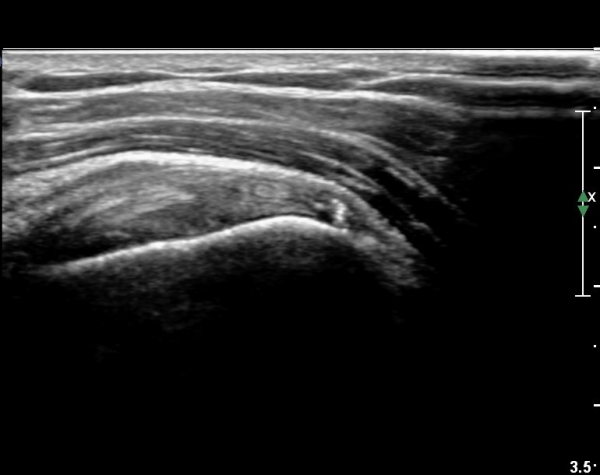

ÀÌµÎ¹Ú±Ù°Ç Á¾´Ü¸é°Ë»ç¿¡¼­ °üÀý³» ¼ö¾×Àú·ù°¡  °üÂûµÈ´Ù(»çÁø 3).